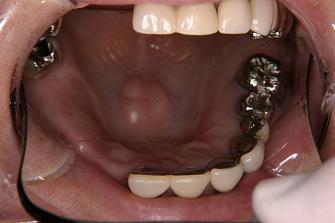

3.

バネなし入れ歯を入れた

状態です!!

* 金属のバネがないので

見栄えが良いです!

入れ歯が入っているとは

気がつかれにくいです!!